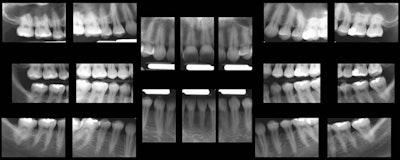

The extracted 18 images from the pano image. Total time to create the survey: 15-20 seconds, versus 20 minutes for a full-mouth intraoral survey. Images courtesy of Dr. Robert Langlais.